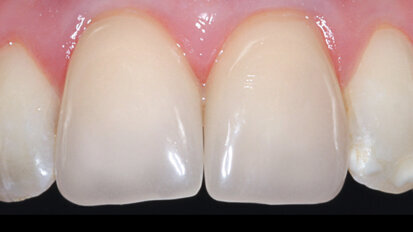

Management kosti a měkkých tkání při komplexní rekonstrukci jednoho zubu implantátem

Rekonstrukce jednoho frontálního zubu implantátem bývá pravděpodobně největší estetickou výzvou pro praktického zubního lékaře. Správné ...